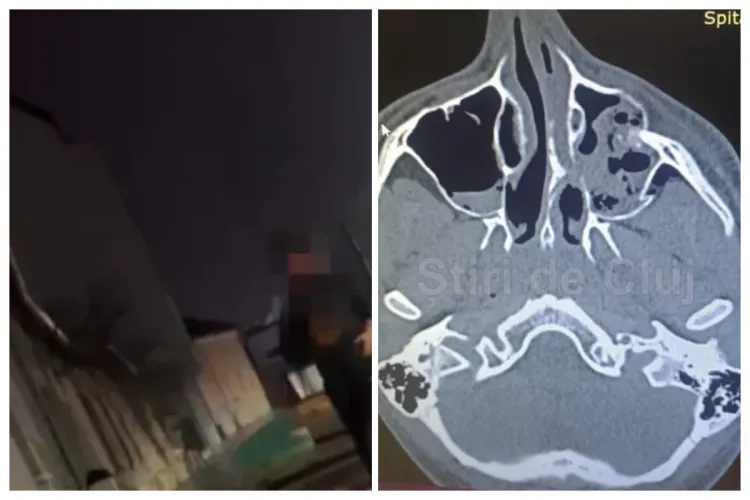

Victima a suferit fracturi multiple la nivelul feței și orbitei, fiind internată în spital și urmând să fie supusă cel puțin două intervenții chirurgicale, una dintre ele implicând montarea unei plăci. Mama băiatului a relatat pentru Știri de Cluj tot ce s-a întâmplat.